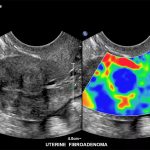

Imagini clinice:

Aplicatii: